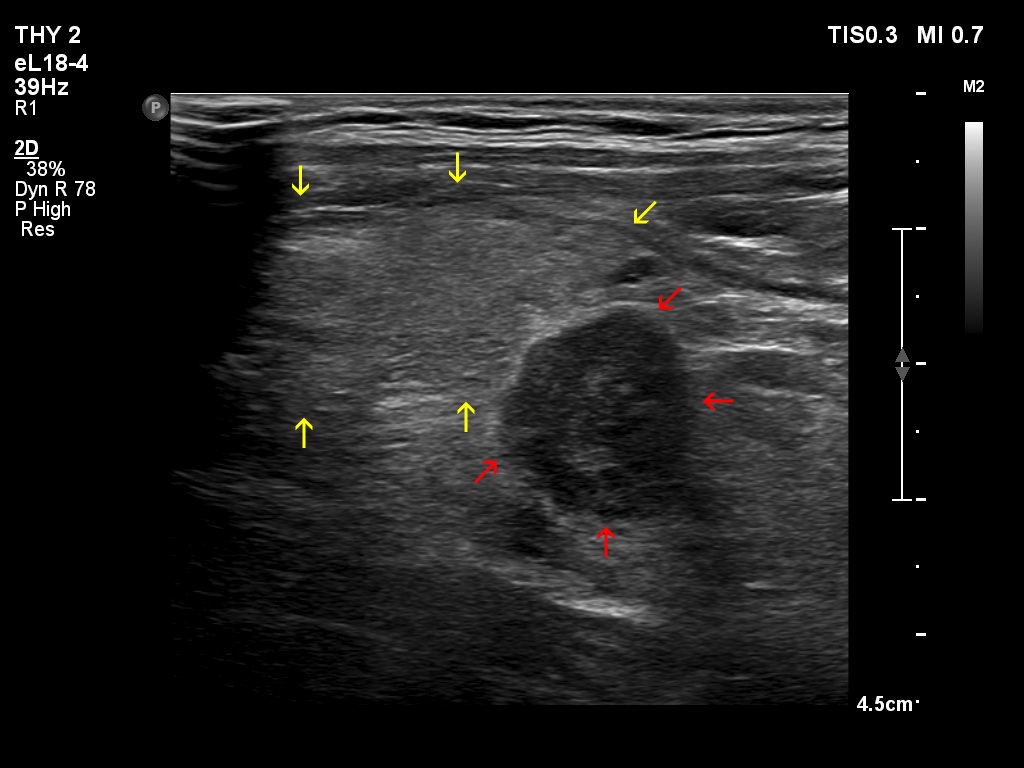

Right lobe, longitudinal scan

Left thyroid bed, longitudinal scan. The thyroid parenchyma is marked with yellow arrows, while the hypoechoic mass is with red ones.